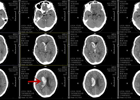

三维定向微创置管 让脑出血的治疗不再“脑洞大开”